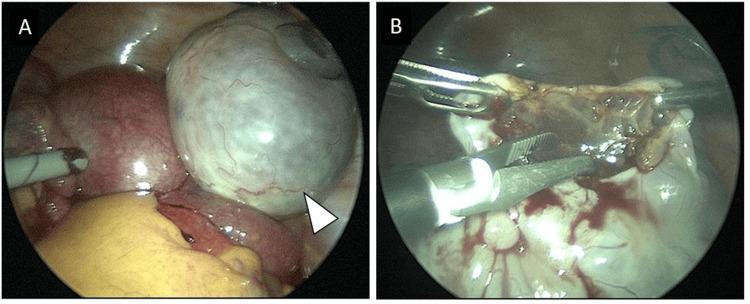

Massive ovarian edema (MOE) is a rare benign condition presenting as unilateral ovarian enlargement with stromal edema, and only a limited number of MOE cases during pregnancy have been reported. MOE is often complicated by ovarian torsion, which requires detorsion. Although the diagnosis of MOE can be made using ultrasound and magnetic resonance imaging, its rarity makes diagnosis difficult, usually leading to overtreatment. Preserving the ovary in the treatment of MOE torsion is essential, and consideration of oophoropexy after detorsion is often reported. However, fixing an enlarged ovary to the pelvic wall in the limited space of the pelvis is challenging. Herein, we present a case of MOE of the right ovary diagnosed at the fifth week of gestation after ovulation induced by clomiphene citrate. Torsion of the ovary occurred in the seventh week. We achieved preservation of the ovary through laparoscopic surgery with detorsion and drainage by making a small incision to the enlarged ovary, resulting in an immediate size reduction. There was no recurrence of torsion or MOE throughout the pregnancy, and the patient gave birth in the 39th week of gestation. This is the third reported case of MOE after ovulation using clomiphene citrate, and it highlights the effectiveness of treatment with detorsion and a small incision of the ovary via laparoscopic surgery in patients with MOE torsion during pregnancy.

摘要

巨大卵巢水肿(MOE)是一种罕见的良性疾病,表现为单侧卵巢肿大伴间质水肿,妊娠期间仅有少数MOE病例的报道。MOE常并发卵巢扭转,需要进行扭转复位。虽然MOE的诊断可通过超声和磁共振成像做出,但其罕见性使得诊断困难,通常导致过度治疗。在MOE扭转的治疗中保留卵巢至关重要,扭转复位后常考虑卵巢固定术。然而,在骨盆有限的空间内将肿大的卵巢固定于骨盆壁具有挑战性。在此,我们报告一例在枸橼酸氯米芬诱导排卵后妊娠第5周诊断为右侧卵巢MOE的病例。卵巢在第7周发生扭转。我们通过腹腔镜手术进行扭转复位和引流,在肿大的卵巢上做一个小切口,使卵巢立即缩小,从而成功保留了卵巢。整个孕期未再发生扭转或MOE,患者在妊娠第39周分娩。这是第三例报道的枸橼酸氯米芬促排卵后发生MOE的病例,它突出了腹腔镜手术对妊娠期间MOE扭转患者进行扭转复位和卵巢小切口治疗的有效性。